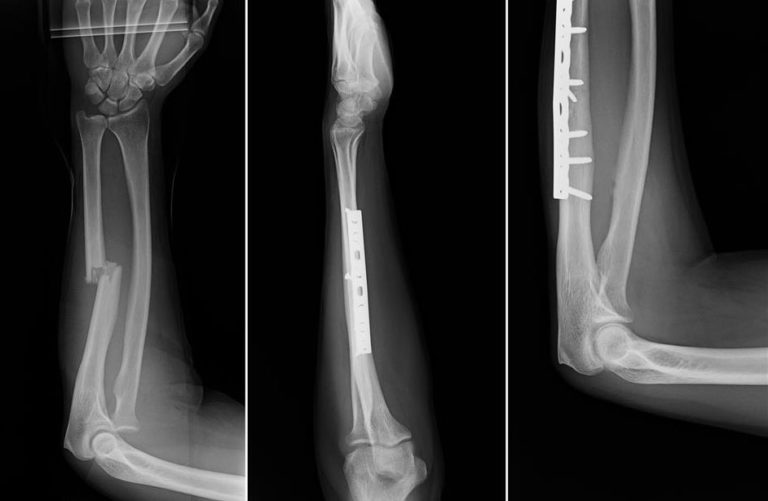

From www.orthoinfo.org

Adult Forearm Fractures OrthoInfo AAOS Pain On Ulna Bone ulnar wrist pain (pain on the pinkie side of the wrist) is very common. ulnar wrist pain, while at rest or with movement, is a common sign of many different injuries and medical. The pain can become severe enough to. It can result from injury to bones, cartilage, ligaments or tendons. ulnar wrist pain occurs on the. Pain On Ulna Bone.

From orthopaedicprinciples.com

Ulnar sided Wrist Pain — Pain On Ulna Bone the most common issues that affect the ulna are fractures, osteoporosis and damage to the ulnar nerve. ulnar wrist pain is so common that it can sometimes be difficult to determine the exact cause. ulnar wrist pain (pain on the pinkie side of the wrist) is very common. ulnar wrist pain, while at rest or with. Pain On Ulna Bone.